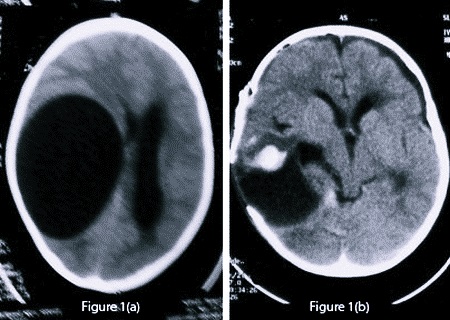

Маленькие по размеру образования обычно отличаются субклиническим течением и поэтому их выявляют совершенно случайно путем нейровизуализирующего обследования головы. Если же киста имеет достаточно большие объемы, то из-за ограниченного интракраниального пространства она может стать причиной развития внутричерепной гипертензии, впоследствии чего произойдет сильное сдавливание соседних мозговых структур.

- арахноидальная. Она может локализоваться как на поверхности, так и в слоях оболочки. Кистозная капсула наполнена ликвором. Чаще всего ее диагностируют у представителей сильной половины человечества в разном возрасте, обычно это киста височной доли. Когда значение внутреннего давления в опухоли превышает показатель давления внутри черепной коробки, она начинает давить на мозговую кору. При увеличении подобных новообразований в размере может появиться тошнота вплоть до рвоты, судороги и галлюцинации. Когда внутреннее содержимое начинает увеличиваться в объеме, у пациента может воспалиться мозговая оболочка. Эта патология требует обязательного обращения в медучреждение, так как при апоплексии кисты может наступить смерть;

- трепанация черепа. Это очень эффективная, но опасная операция, в ходе которой есть высокий риск повреждения головного мозга.